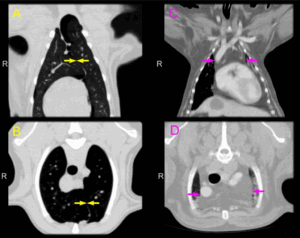

Увеличение тех, которые находятся в труднодоступных местах, можно диагностировать с помощью компьютерной или магнитно-резонансной томографии , ультразвукового исследование. Также всегда назначается общий анализ крови и мочи.

Ревматоидная лимфаденопатия.

Лимфаденопатия при ревматоидном артрите не ограничивается лимфоузлами, собирающими лимфу от пораженных суставов, но как составная этого системного заболевания часто может иметь генерализованный характер. Развивается выраженная фолликулярная гиперплазия. Увеличенные центры размножения могут содержать аморфные ШИК-по-штивные гиалиновые включения; изредка фолликулярная гиперплазия может сопровождаться появлением саркоидоподобных гранулем.

Большие количества плазмоцитов, часто с тельцами Расселя, инфильтрируют мозговые тяжи и могут также определяться в центрах размножения.